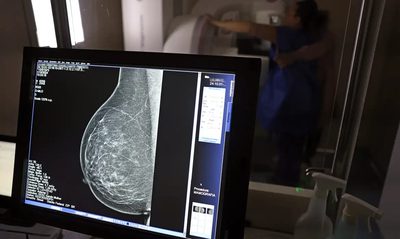

Descobrir o câncer de mama no início pode mudar destinos. Mais do que estatísticas, significa dar às pessoas a chance de seguir vivendo suas histórias. Neste Outubro Rosa, a Empresa Brasileira de Serviços Hospitalares ( Ebserh ), que administra 45 hospitais universitários federais, adere às novas recomendações do Ministério da Saúde. A partir de agora, quem tem entre 40 e 49 anos também terá acesso à mamografia pelo Sistema Único de Saúde (SUS).

Até então, o rastreamento era indicado a partir dos 50 anos. A atualização foi definida porque, segundo o Ministério da Saúde, a faixa etária dos 40 aos 49 anos concentra aproximadamente 23% dos casos de câncer de mama no Brasil. Além disso, houve ampliação da idade máxima para o exame: se antes era recomendado até os 69 anos, agora se estende até os 74 anos. Na Rede Ebserh , 24 hospitais ofertam mamografia. Somente no ano de 2024 , foram realizados mais de 54 mil exames.

O mastologista do Hospital de Clínicas da Universidade Federal de Uberlândia (HC-UFU), Donizete Willian Santos, afirma que “o diagnóstico precoce, principalmente com o rastreamento mamográfico, pode diminuir a mortalidade pelo câncer de mama em até 40% quando iniciado aos 40 anos na população de baixo risco. Além disso, reduz a necessidade de quimioterapia e o tempo em terapias complementares, como o bloqueio hormonal”.

Para o especialista, o autoconhecimento do corpo continua sendo um aliado importante. No Brasil, apenas 37% das mulheres em idade alvo realizam a mamografia, enquanto a recomendação da Organização Mundial da Saúde (OMS) é de 70%. “Embora o autoexame não diminua a mortalidade, ele conscientiza a mulher sobre a necessidade de realizar a mamografia e pode levá-la a procurar o serviço de saúde mais cedo, melhorando muito os resultados oncológicos”, explica.